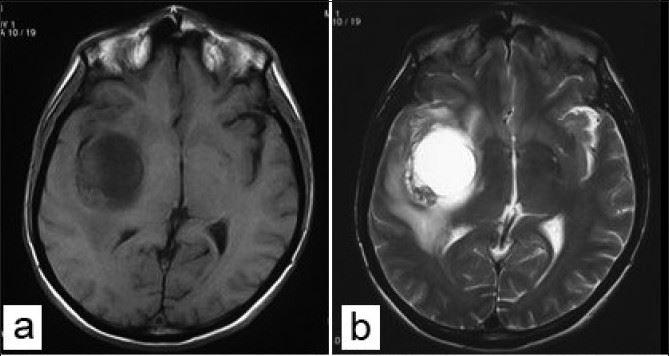

ガドリニウム:MRIで造影といえばこれ。 超磁性体酸化鉄粒子 SPIO:肝網内系をターゲットとした造影剤である。SPIOはKupffer細胞に貪食されリソソームにクラスター化される家庭でT2*緩和時間およびT2緩和. くはない3).mriでは,鉄沈着による局所の磁場 の不均一により,t1,t2及びt2*緩和時間が 短縮する特性を利用して肝内鉄沈着の評価が可 能である.特にt2及びt2*とそれらの逆数であ るr2及びr2*は鉄濃度と比例して変化するた 一口メモ 図3 肝生検組織所見. 頭部mriの見方です。 基本は 水 = 脳脊髄液 を見ます。 脳脊髄液は脳室や脳の表面にあります。 t1なら黒 t2なら白です。 話が難しいのは mriに….

〈medix vol.50〉 41 1.はじめに mri検査において基本シーケンスはt2強調画像とt1強調 画像である。かかりつけ医の医療の場において、診断能向上の. 頭部MRI の基礎 -頭部MRI で撮られる各画像について- 友愛会南部病院 仁井田 明 要旨 現在、日常的に撮影されている頭部MRI(Magnetic resonance imaging :磁気 共鳴画像法)画像にはT1 強調像(T1WI)、T2 強調像(T2WI)、プロトン密度強 調像(PDWI)あるいはFLAIR(FLuid-Attenuated Inversion Recovery)像. 3T MRIの組織コントラスト能の特徴 T1強調画像 de Bazelaireらの研究 1) によると,腹部領域における3Tと1.5Tの緩和時間の違いは,肝臓,脾臓,膵臓では,3TでT1値が著明に延長するのに対し,筋肉では緩和時間に差がなく,結果的に,3Tでは肝臓,膵臓,筋肉でのT1値の差が少なくなる。.